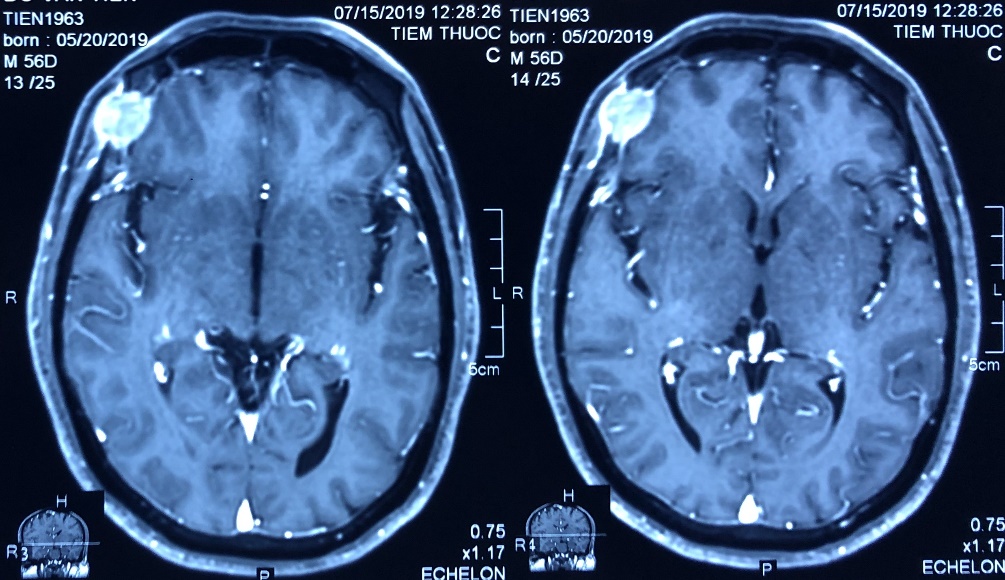

– Chụp PET/CT với F-18 FDG:

U thùy giữa phổi phải kích thước 23x32mm, tăng hấp thu FDG, max SUV=8,13, xâm lấn màng phổi. Ngoài ra nhu mô phổi phải còn một vài nốt mờ, nốt lớn nhất kích thước 16x10mm, tăng hấp thu FDG, max SUV=4,37.

Dày lan tỏa màng phổi phải, tăng hấp thu FDG, max SUV=5,43. Tràn dịch màng phổi phải dày 38mm.

Nhiều hạch trung thất, hạch nách, kích thước lớn nhất 15x13mm, tăng hấp thu FDG, max SUV=4,75.

Tổn thương xương đa ổ: xương sườn 2 bên, các đốt sống, xương cùng S1, xương chậu hai bên, xương đùi phải, max SUV=9,79.

Hình 3: Hình ảnh chụp PET/CT: u phổi phải di căn hạch, màng phổi, di căn xương đa ổ